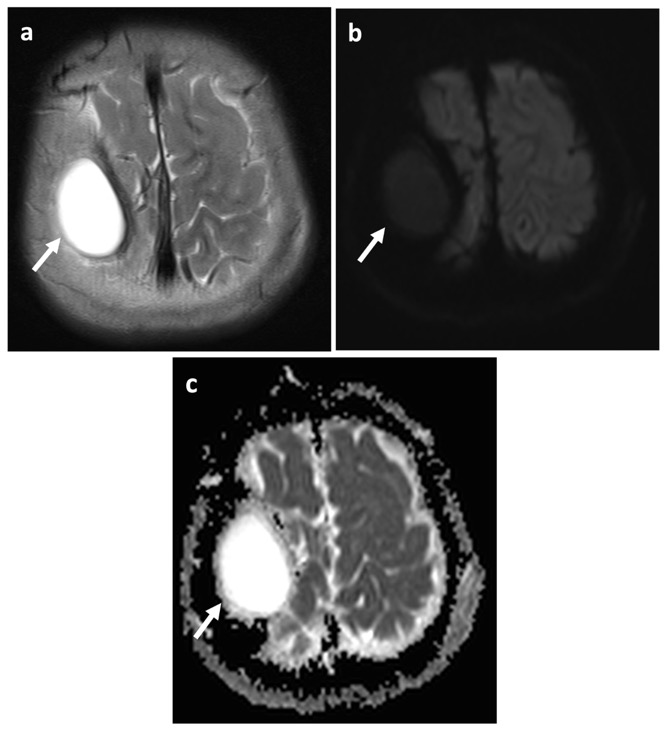

MR: DD du kyste épidermoïde